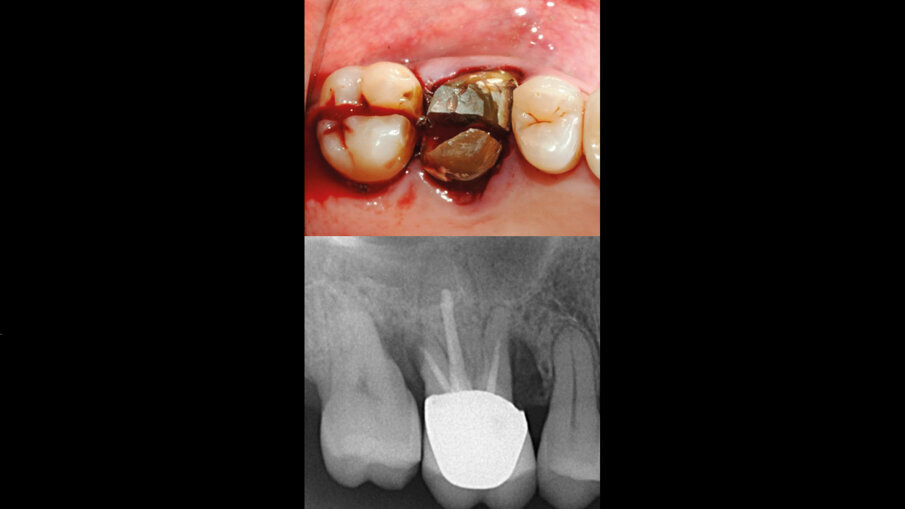

Il caso clinico tratta di una donna di 63 anni che giunge alla nostra osservazione presso il centro odontoiatrico civitali di Milano, presentando gli elementi 26 e 27 non recuperabili e richiedendo una riabilitazione fissa (Fig. 1). Verificata la presenza di osso residuo sufficiente a garantire il corretto posizionamento implantare, nonostante una condizione ossea discretamente compromessa, abbiamo ritenuto che con appropriata tecnica chirurgica estrattiva attua a salvaguardare i profili ossei e il setto inter-radicolare abbinata a una macromorfologia implantare idonea, si potesse ottenere un buon livello di stabilità primaria. Per ripristinare e mantenere i volumi ossei si è quindi optato per un posizionamento implantare immediato associato a un mantenimento di volume osseo della cresta ossea vestibolare. Per colmare lo spazio residuo formatosi successivamente all’estrazione delle radici vestibolari degli elementi si è optato per l’utilizzo di un innesto osseo costituito da un cilindro di pasta ossea liofilizzata di origine equina (Bio-Gen Putty, Bioteck Spa) protetto da una matrice collagenica tridimensionale (XC COLLAGEN Xenomatrix, Bioteck Spa).

Fig. 1 - Visione occlusale che mostra gli elementi 26-27 irrecuperabili. Sotto, l’RX iniziale.